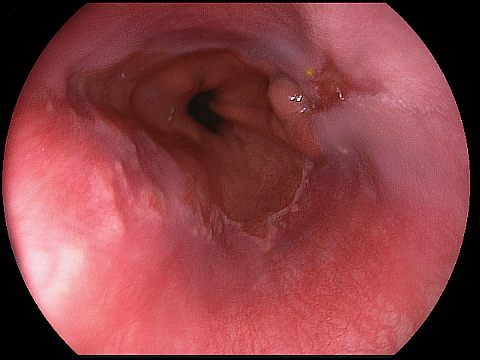

Reflux oesophagitis grade D according to the Los Angeles classification